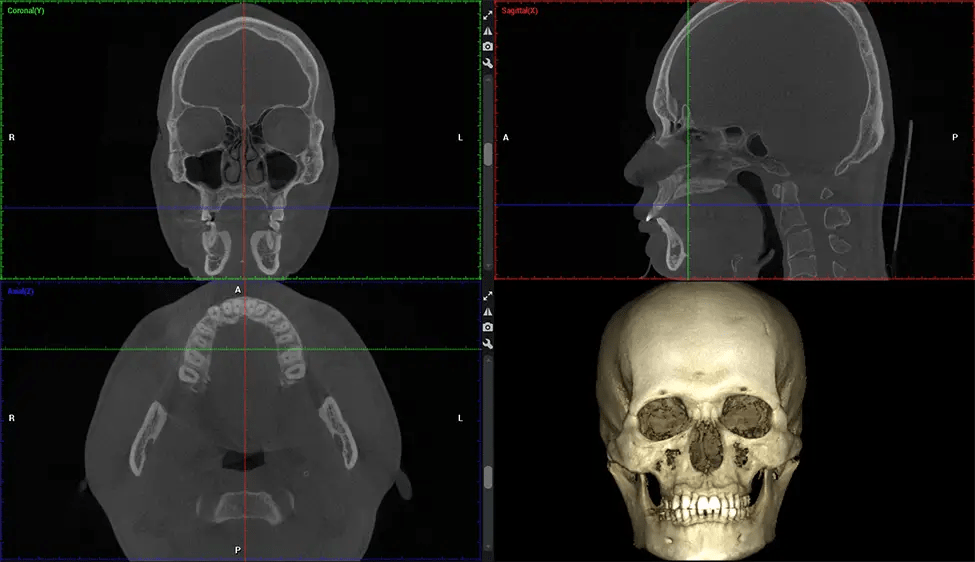

Cone Beam Computed Tomography (CBCT) is an advanced imaging technique used in dentistry and maxillofacial surgery to obtain detailed 3D images of the oral and maxillofacial structures. At Dr G Dental Studio, our CBCT scanners utilize a cone-shaped X-ray beam and a specialized detector to capture images from different angles. A computer then combines these images to create a 3D representation of the patient’s oral anatomy.

This 3D scan, called cone beam computed tomography, gives your dentist a more complete image of your oral anatomy and disease processes than a traditional X-ray. Unlike conventional X-rays, which capture a 2D image of your mouth from various angles, a 3D scan takes multiple digital X-rays for one image. It provides a complete view of your jaw, teeth, nerves, and soft tissues. This enhanced view allows dentists to detect minor issues not visible in traditional 2D scans, such as impacted wisdom teeth or bone fractures in the sinus cavity.

There are many benefits to using CBCT technology, especially compared to the traditional 2D X-ray format. One of the most significant advantages of CBCT scans is that they provide much more information than traditional X-rays. A scan lets your dentist see images from all angles of your jaw and mouth, including your sinuses, nasal cavity, cheekbones, and other surrounding areas. This added information helps your dentist craft a comprehensive treatment plan that addresses all aspects of your oral health.

Planmeca Viso G7 CBCT ( Cone Beam CT Scan ) is designed to surpass the demands of industry leaders, specialists, and large institutions. It’s has a large ø25×30 cm sensor with four built-in cameras. It can capture unlimited volume sizes from a ø3×3 cm to a ø30x30cm volume capturing the skullcap through C7 on the cervical spine. The Planmeca Viso G7 offers the industry’s largest single volume scan of ø30×19 cm. It’s poised to handle advanced imaging modalities such as Planmeca ProFace® and Planmeca 4D™ Jaw Motion technology. The occipital head support allows an unimpeded view of facial tissue.

Planmeca is the only manufacturer clinically proven to dramatically reduce patient radiation without sacrificing image quality. Planmeca Ultra Low Dose™ achieves an average reduction in dose of 77% without a statistical reduction in image quality allowing doctors to incorporate 3D imaging into routine protocols with effective patient radiation often lower than 2D intraoral imaging. This increases patient care, allows doctors to diagnose more dentistry, and often earlier in disease progression, than with 2D imaging alone.